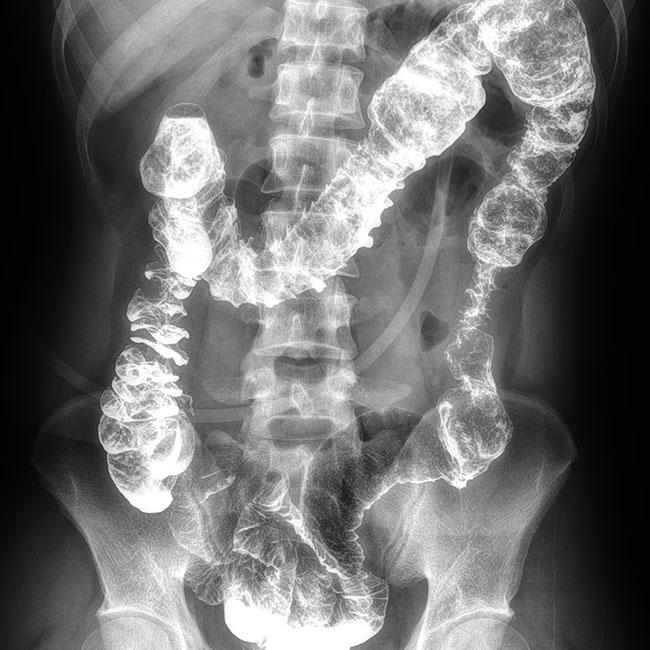

臨床樣本